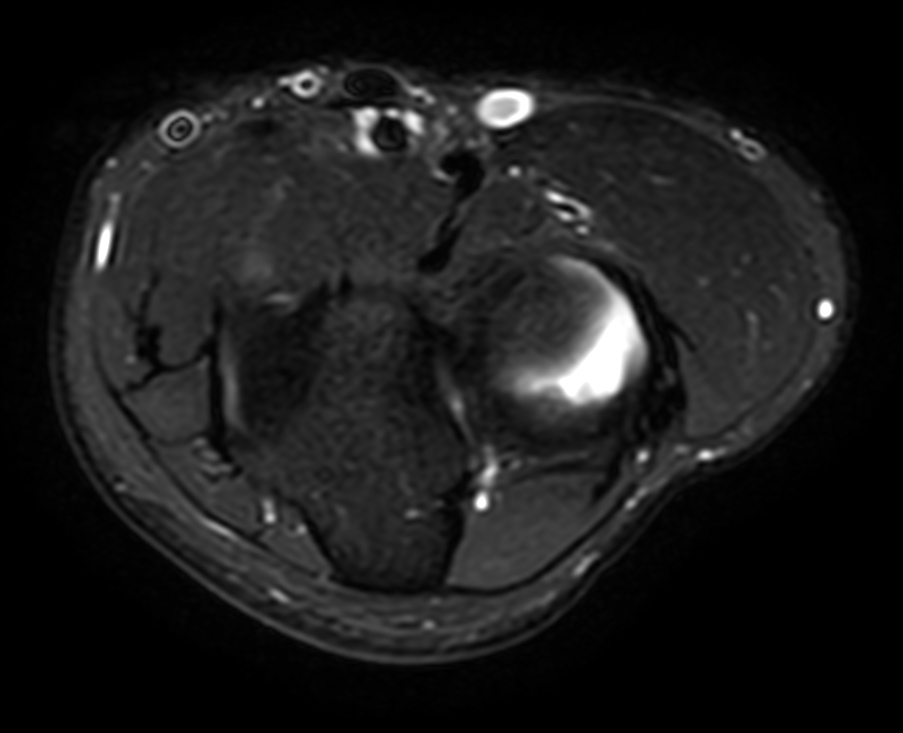

High quality Elbow imaging with Compressed SENSE

Spital Uster, Switzerland